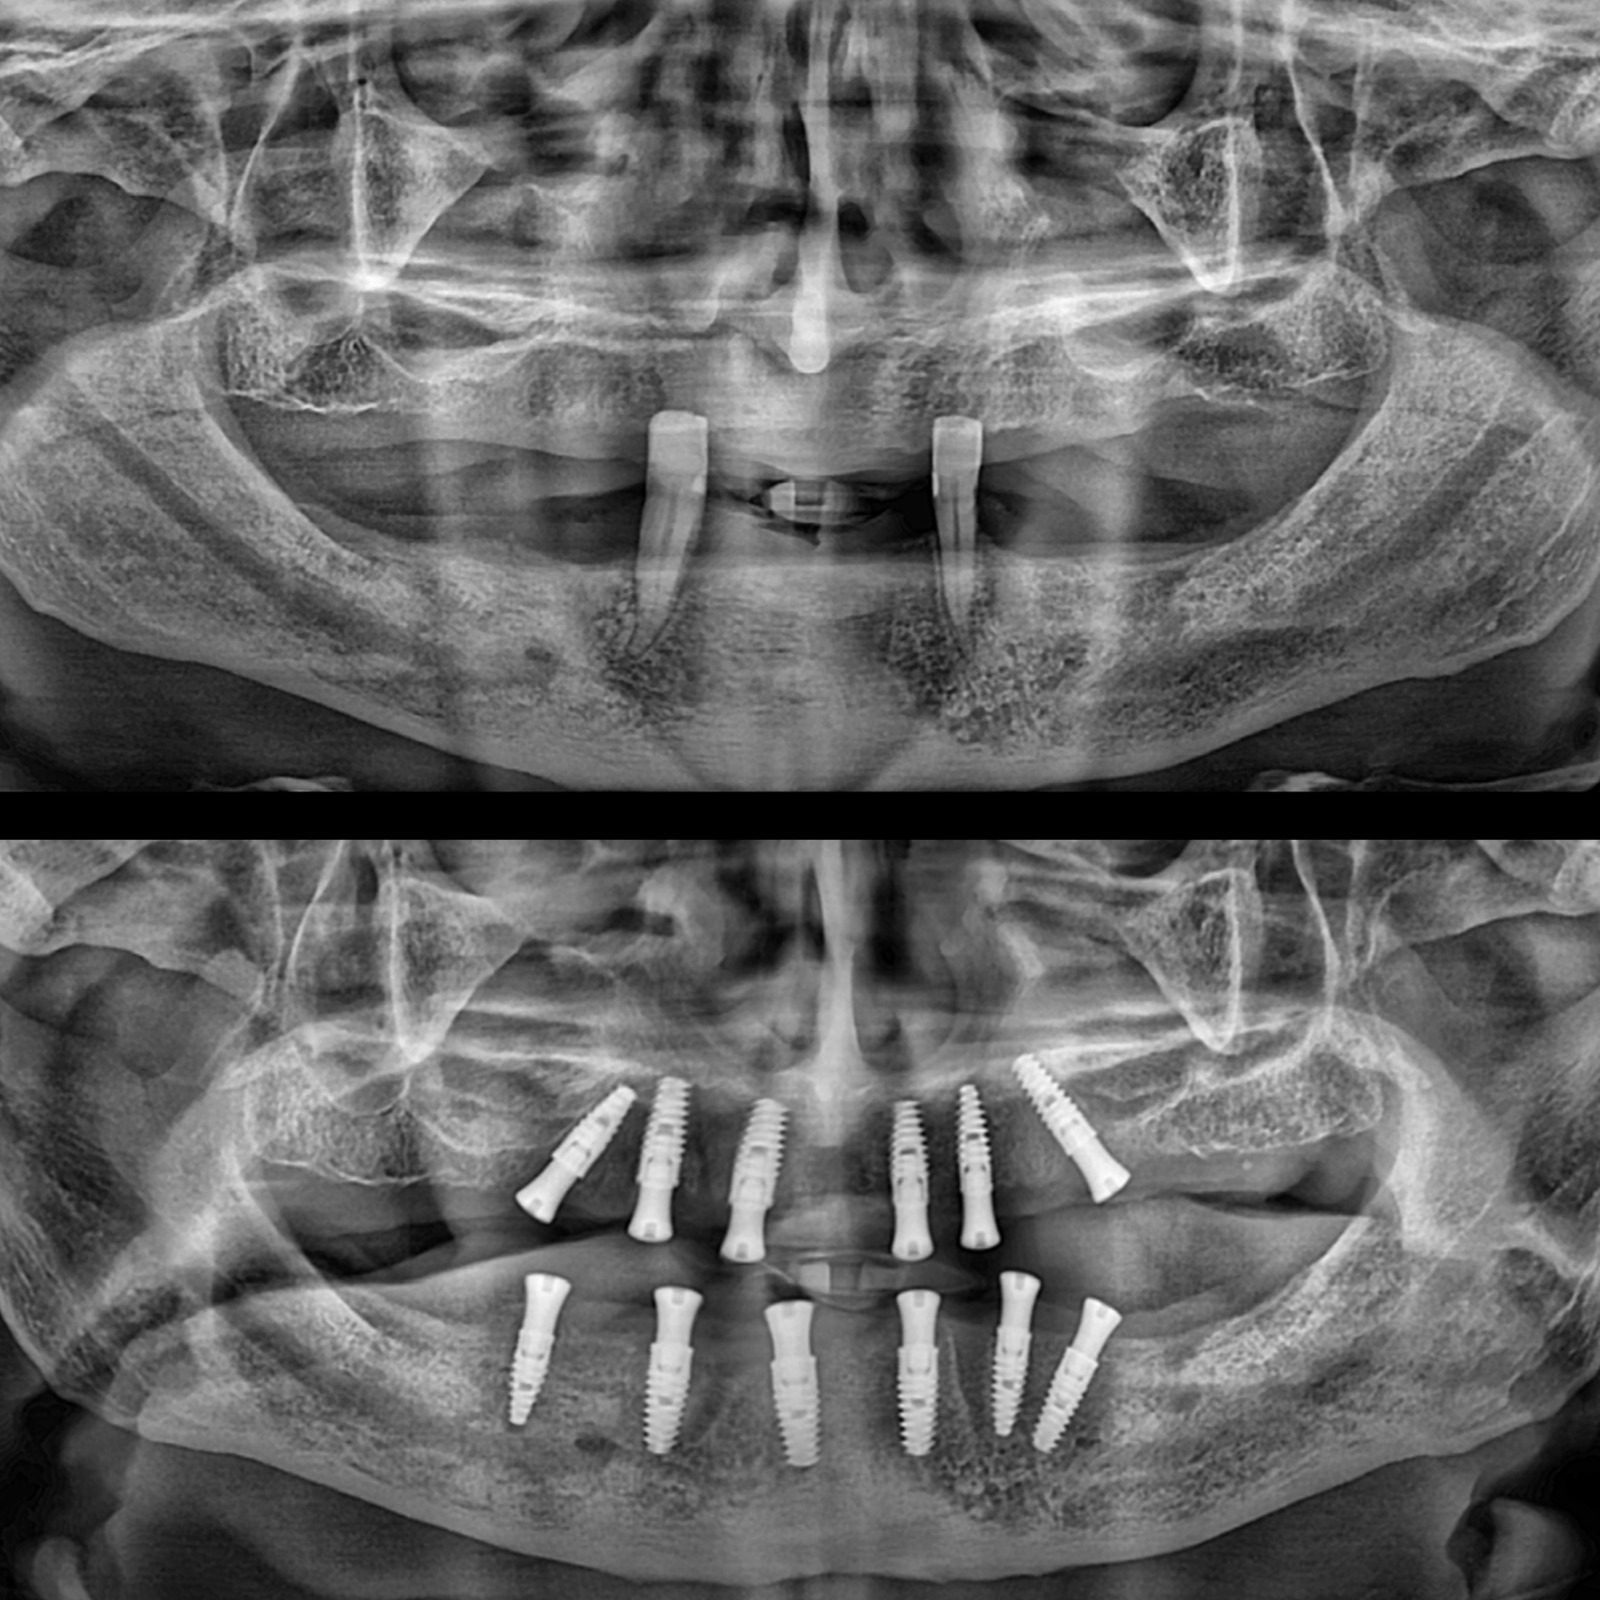

- Çene Cerrahı hastanın genel sağlık durumunu ve ağız yapısını değerlendirir.

- Röntgen ve Bilgisayarlı Tomografi (BT) gibi görüntüleme teknikleri kullanılarak çene kemiği yapısı incelenir.

4-) İmplant Yerleştirme

- Diş hekimi çene kemiğine bir kesik açarak implantın yerleştirileceği alana erişir.

- Titanyum implant çene kemiğine vidalanır.